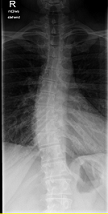

Röntgenbilder

- TSPINE seitlich (oberer Abschnitt)

T bedeutet Top Spine? - TSPINE Bild 2 vk II.png (25.02 KiB) 19749 mal betrachtet

deine Bilder lassen vermuten, dass vielleicht gar nicht die Skoliose dein Problem ist, sondern dein sagittales Profil. (Steht dein Kopf ziemlich nach vorne, wenn du dich vin der Seite betrachtest?) solltest auf jeden Fall einmal zum Spezialisten, im deine Situation kompetent abklären zu lassen. Aus NRW ist wahrscheinlich Dr. Verres in Bingen am nächsten.

mit dem sagittalen Profil meint man das Profil von der Seite gesehen. Laut deinen Aufnahmen hast du eher eine geringe Skoliose, aber einen ziemlichen Rundrücken und Hohlkreuz was auch Beschwerden machen kann und das die Ärzte auch gerne übersehen oder nicht sehen wollen. Deshalb ist es auch wichtig, einen Spezialisten aufzusuchen, der dies auch mit behandeln kann. Leider ist dies keine Ganzaufnahme, dann würde man das eher sehen. Es gibt hier schon genug Berichte, die das mit Hyperkyphose und -lordose gut beschreiben. Also lesen bildet...

Dem kann ich mich nur anschliessen, es sieht sehr nach Rundrücken (Bild 2-Hyperkyphose) und Hohlkreuz (Bild 1-Hyperlordose) aus.sloopy hat geschrieben:deine Bilder lassen vermuten, dass vielleicht gar nicht die Skoliose dein Problem ist, sondern dein sagittales Profil.

Deine Brustwirbelsäule macht aber, jetzt nachdem ich nochmal hingeschaut habe, tatsächlich den Eindruck, als würdest du eine Hyperkyphose haben und dein Kopf sich nach vorne legt, zumindest wenn ich deine Halswirbelsäule, auf dem Bild und in meiner Phantasie, weiter zeichne.

Zu einer Hyperkyphose gehört auch meistens eine begleitende Skoliose unter 10°. Fällt diese über 10° aus (Die med. Definition einer Skoliose erfordert minds. 10°), spricht man von einer Khyposkoliose.